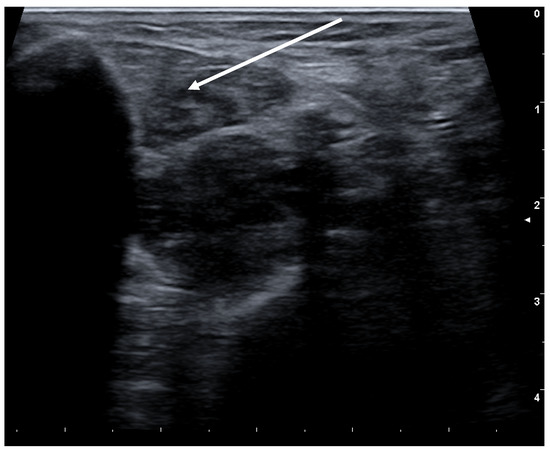

- Flexion of the toes:This second form usually causes more discomfort to the patients, as it induces involuntary movements in the toes, in particular the small ones, but also the big toes. It occurs frequently as exercise-induced dystonia. Here, a distinction has to be made whether only one of the two or both toe flexing muscles are involved. The short flexor is found in the sole of the foot, the long flexor in the lower calf. Here too the injection into the muscle is performed under ultrasonic guidance (see Figure 4).